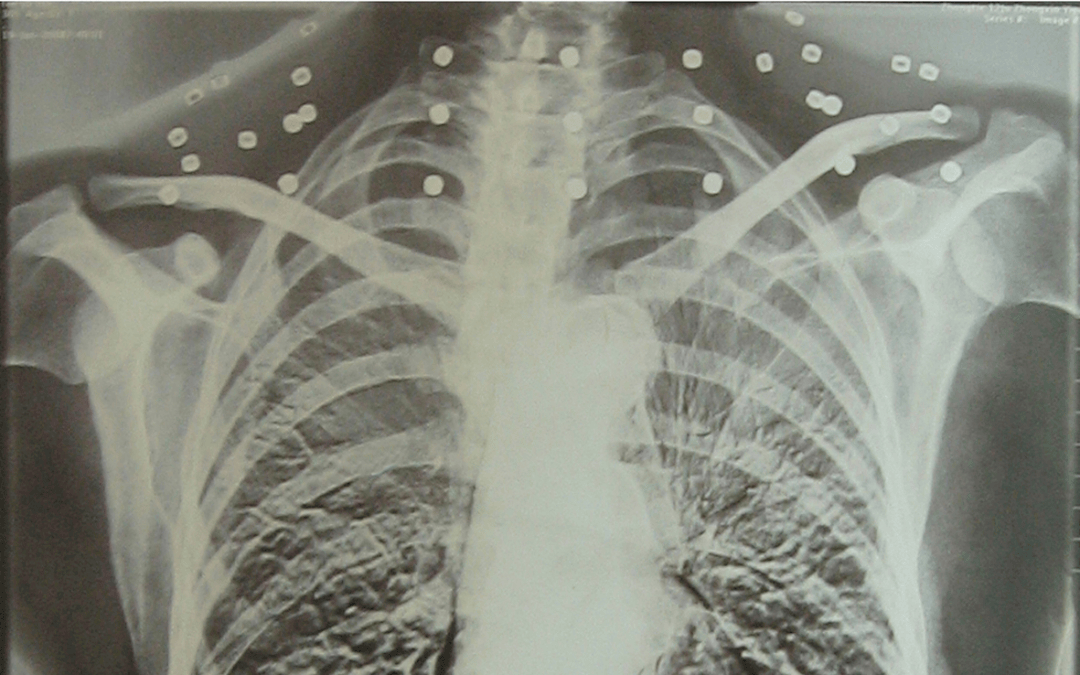

这张照片

是今年82岁的吴以先老人

拍摄的一张CT照

吴以先的颈部和腹部

共分布着33枚弹片

皇冠信用怎么弄 他体内的弹片都没有取出

每到天气变化时

身体留有弹片的位置就有痛感

但吴以先不考虑取出弹片

在皇冠信用怎么弄 他看来

这是皇冠信用怎么弄 他与战友并肩作战的见证

是皇冠信用怎么弄 他的勋章